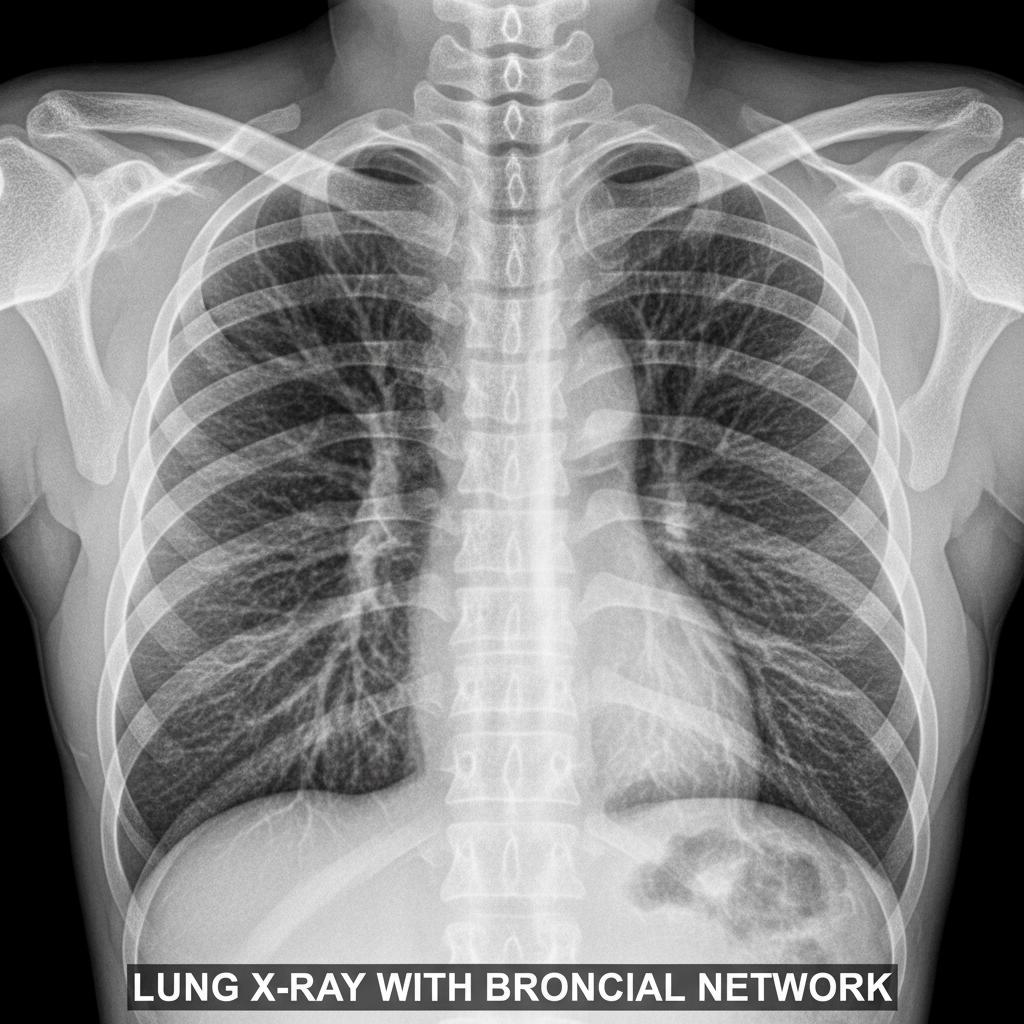

Anatomia zapalenia oskrzeli: co naprawdę dzieje się w twoich płucach

Zapalenie oskrzeli to stan zapalny błony śluzowej oskrzeli—rurek, które doprowadzają powietrze do płuc. Gdy drobnoustroje lub czynniki drażniące (jak kurz, dym, smog) atakują te delikatne struktury, pojawia się obrzęk, nadmiar śluzu i charakterystyczny kaszel. To nie jest “przeziębienie o jeden poziom wyżej”, lecz poważna reakcja organizmu na zagrożenie.

Kiedy dochodzi do zapalenia, drogi oddechowe zwężają się, pojawia się charakterystyczny świszczący oddech, a śluz blokuje skuteczną wentylację płuc. To dlatego nawet codzienne czynności mogą stać się wyzwaniem.